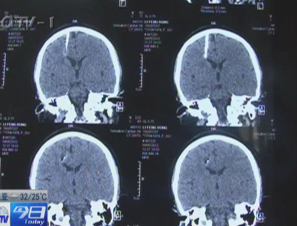

• 女子头颅惊现5厘米铁钉 颅内待了30多年